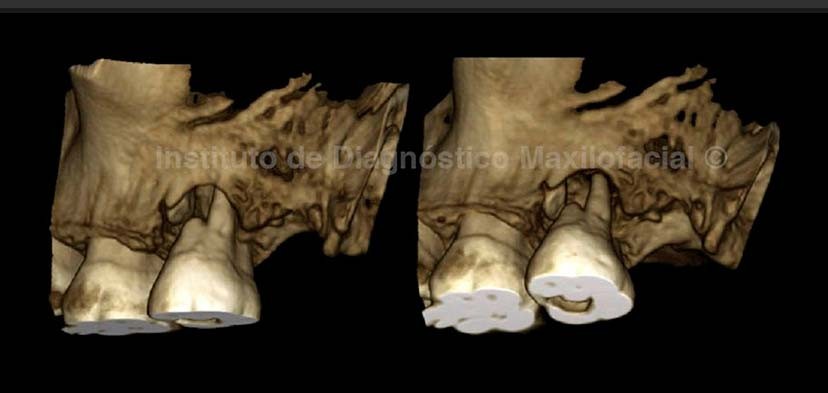

La tomografía computarizada de haz cónico (cone beam), en cortes transaxiales, tangenciales y reconstrucción 3D; nos muestra un trazo de fractura a nivel del tercio cervical de la raíz mesial de la pieza 27 (Fig 2 ,3 y 4).Así mismo observamos un proceso osteolítico perirradicular extenso que condiciona la reabsorción de las raíces distovestibular y palatina, además del engrosamiento de la mucosa sinusal, la reconstruccion 3D confirma todos estos hallazgos.(Fig.2 ,3 y 4).